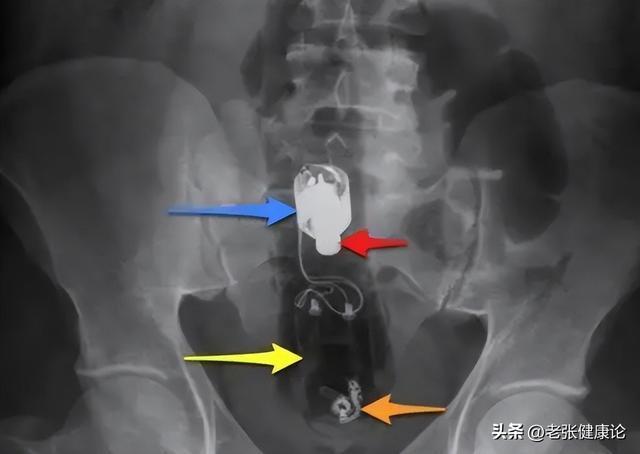

直到有一天,大便上出现了一圈鲜红色的血,他被家人“半拖半拽”送进医院。做完肠镜,医生沉默了一会儿,说出结果:肠道恶性肿瘤,已经不算早期。

大便形状变细、变扁,像“铅笔条”。很多被确诊为结直肠癌的病人,回想起来都有类似感受:“以前大便粗壮、成型,现在老是细细长长、扁扁的一条。”

这可能说明肠腔内有东西占地方,让粪便通过的“通道”变窄。并不是每一次形状改变都代表肿瘤,但持续出现、且越来越细,就不应只当作“上火”看待。

不明原因的便血或大便发黑。颜色鲜红:多见于靠近肛门的下消化道出血,如直肠、肛管病变。颜色暗红、夹杂黏液:可能提示更上方肠道有问题。

柏油样黑便:像沥青、味道臭,要高度警惕上消化道或部分结肠出血。痔疮也会出血,但痔疮出血往往伴随排便时肛门明显疼痛、瘙痒或肿物脱出。